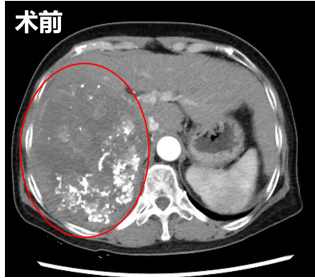

发现肝癌时 却被告知没有手术条件

时间拉回2023年7月,65岁的苏阿姨开始出现上腹部疼痛,就诊当地医院被诊断为:“巨大肝癌、肿瘤晚期”,辗转多家县市级医院均被告知无法进行手术切除,这对苏阿姨及家属来说,无疑是个晴天霹雳。约一个月后经人介绍,她抱着一线希望,来到宁德市医院肝胆胰脾外科主任医师林德新门诊。经肝脏MRI增强检查提示,肝右后叶巨大肿瘤,直径约16cm且门脉右支被肿瘤包绕,初步诊断为“右肝巨大肝细胞癌(CNLC分期-Ⅲa期),且苏阿姨存在严重肝硬化情况,贸然手术极易出现小肝综合征或肝衰竭(残肝体积仅剩40%)。面对苏阿姨及家属的期待,林德新团队决定全面评估患者身体条件,根据肝癌治疗经验并结合其他患者的成功案例,为患者争取手术机会。

经过全面评估,林德新团队最终决定先行术前综合治疗(TACE局部+靶向药物+免疫联合治疗),待肿瘤缩小后再评估手术可行性。因苏阿姨病情复杂,医疗团队邀请介入科、肿瘤内科进行多学科会诊(MDT),充分探讨病情。入院一周后,医疗团队先予以苏阿姨“经导管肝动脉栓塞术+动脉化疗栓塞”,积极保肝、抗乙肝感染及营养支持等治疗,并先后给予4个周期的靶向+免疫联合抗肿瘤治疗。经过3个月综合治疗,苏阿姨的血清肿瘤标志物进行性下降,值得庆幸的是,复查影像学检查提示:病灶范围较前缩小,原本被肿瘤包绕的门静脉右支不再被绕。事实证明,林德新教授为苏阿姨制定的个性化治疗方案给她带来了希望。

术前,由于苏阿姨存在严重肝硬化,为精准手术切除范围,林德新团队通过对患者肝功能动态监测、病灶三维成像和肝功能储备评估后,为苏阿姨制定了个性化的手术方案——沿前裂静脉的右侧行肿瘤切除(残肝体积可剩50%),这样既保证完整切除肿瘤,又能避免出现小肝综合征、肝衰竭。最终,在麻醉师和手术室的密切配合下,林德新团队成功为苏阿姨施行了:“腹腔镜下右肝巨大肝癌切除术”,手术顺利,切下的肿瘤竟重达3斤!术后第一日,患者即可在护士的协助下下床活动。经过10多天的精心护理,患者逐渐康复。术后病理提示:巨块型肝细胞性肝癌伴大范围坏死(肿瘤坏死百分比约90%)。随着苏阿姨的顺利出院,这无疑是创造了晚期肝癌治疗的又一奇迹。